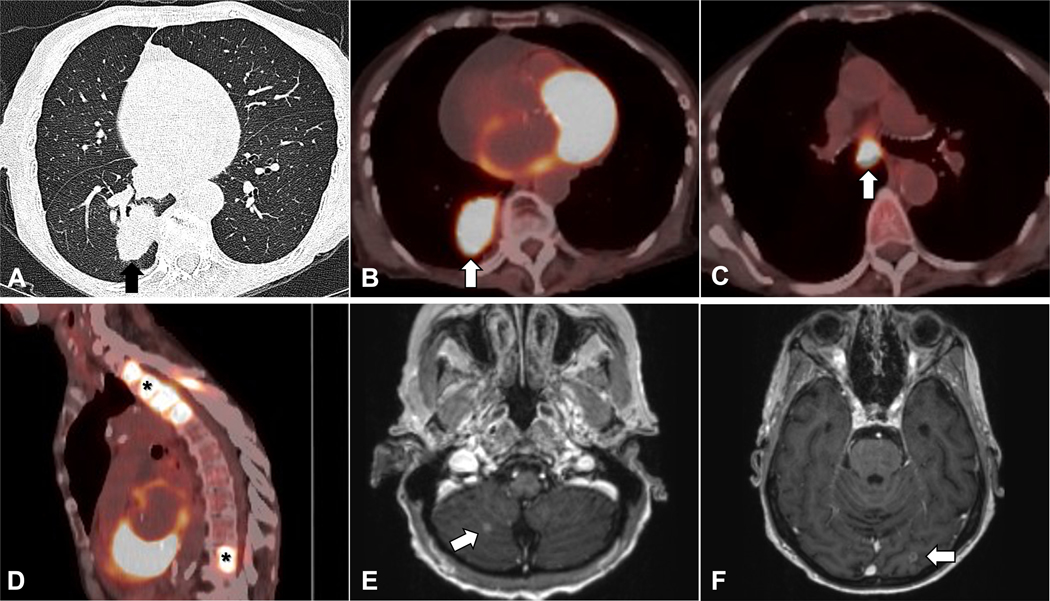

A 70-year-old woman with no history of smoking presented with dyspnea and was found to have a 4 cm lung mass and suspicious thoracic spine lesions with no mediastinal lymphadenopathy (defined as size > 1 cm in the short axis) on a non-contrast CT scan of the chest (Figure 10 A). A request was made for transthoracic needle biopsy of the suspected primary lung tumor rather than the vertebral lesions out of concern that they may fail to provide tissue for biomarker testing. However, because of the size of the mass and high likelihood it represented a primary lung malignancy, a multi-disciplinary tumor board recommended a PET/CT scan to assess for other metastatic disease. The patient’s PET scan demonstrated intense FDG avidity in mediastinal lymph nodes and the bone lesion (Figure 10 B–D). Notably, these lymph nodes were suspicious due to high PET avidity rather than their size. An MRI of the brain with and without contrast demonstrated multiple small enhancing lesions consistent with metastatic disease (Figure 10 E–F). The patient underwent bronchoscopy with EBUS-TBNA, which established a diagnosis of adenocarcinoma. Biomarker testing revealed an EGFR exon 20 insertion mutation. The patient had a rapidly declining performance status and cognitive issues, making her ineligible for chemotherapy or immunotherapy. Treatment with radiotherapy for the brain lesions and mobocertinib were offered and after discussion with the patient and their family, their decision was to forgo further treatment.

Figure 10.

A) Axial images on CT demonstrate a 4 cm lung mass (arrow, A). B-D) PET/CT scan shows FDG uptake in the lung mass (arrow, B), mediastinal lymphadenopathy (arrow, C) and FDG-avid thoracic and lumbar spine lesions (asterisks, D). E-F) Brain MRI scan shows small enhancing lesions suspicious for metastatic disease (arrows, E, F).

Inter-disciplinary collaboration and communication improve cancer care quality and outcomes.62, 63 Inter-disciplinary communication, in the form of tumor board discussion, led to an improved choice for site of biopsy in this case. For patients lacking a confirmed diagnosis, those who have suspicious lesions that appear difficult or risky to biopsy, have already undergone a non-diagnostic procedure, or are being evaluated by physicians with little experience directing the work-up for suspected lung cancer anecdotally benefit from multi-disciplinary discussions. When initial imaging does not reveal a biopsy site with a favorable risk-to-benefit ratio, but advanced or metastatic disease is likely, PET/CT scanning is helpful in identifying the optimal biopsy site. For a lung mass > 3 cm, the likelihood of hilar/mediastinal involvement is high, and invasive mediastinal staging by bronchoscopy or mediastinoscopy would be indicated even with a negative PET scan if a curative surgical approach is contemplated.38 In this case, mediastinal lymph nodes involved with cancer were not detected to be abnormal by CT size criteria but by intense FDG avidity suggestive of disease involvement. Without identification of a more peripheral site, such as cervical lymphadenopathy or distant soft-tissue lesions, bronchoscopy with EBUS-TBNA provides the highest yield for biopsy to establish diagnosis, clinical stage, and provide material for biomarker testing at low risk to the patient.

A transthoracic needle biopsy for this patient would likely provide tissue for diagnosis and biomarker testing, however, it has a higher rate of complications, including an estimated ~15% risk of pneumothorax, compared to the low complication rate offered by bronchoscopy and EBUS-TBNA with ~1% risk of major complications.37, 49, 64–66 Bronchoscopy with EBUS-TBNA has demonstrated success for completing biomarker testing and confirms clinical nodal stage, as in this case. Most laboratories accept formalin-fixed paraffin-embedded biopsy specimens, but not all laboratories are capable of performing comprehensive biomarker testing on certain cytopathologic samples (e.g., touch preparations, direct smears).10 In this case, histologic confirmation of distant metastasis was not deemed necessary because of the overwhelming radiologic evidence of metastatic disease in brain and bone (see Scenarios 5 and 6 for a more detailed discussion of brain and bone sites of metastasis).